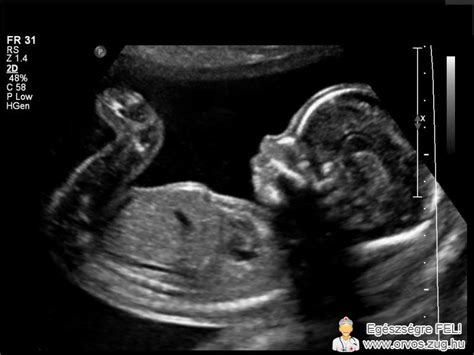

A méhszáj állapotának ellenőrzésére többféle módszer létezik. A legegyszerűbb és leggyakoribb a szülészorvos vagy a bába által végzett kézi hüvelyi vizsgálat. Ez a módszer bár kevésbé pontos és szubjektívebb a hüvelyi ultrahang vizsgálatnál, mégis a legtöbb terhesgondozási találkozáskor és kórházi vizsgálatnál alkalmazzák. Fontos megjegyezni, hogy fenyegető koraszülés esetén a kézi vizsgálat káros is lehet, ha a vizsgáló az ujjával a nyakcsatornába hatol, ezzel tágítva azt, vérzést okozva, és rontva a méhszáj állapotát.